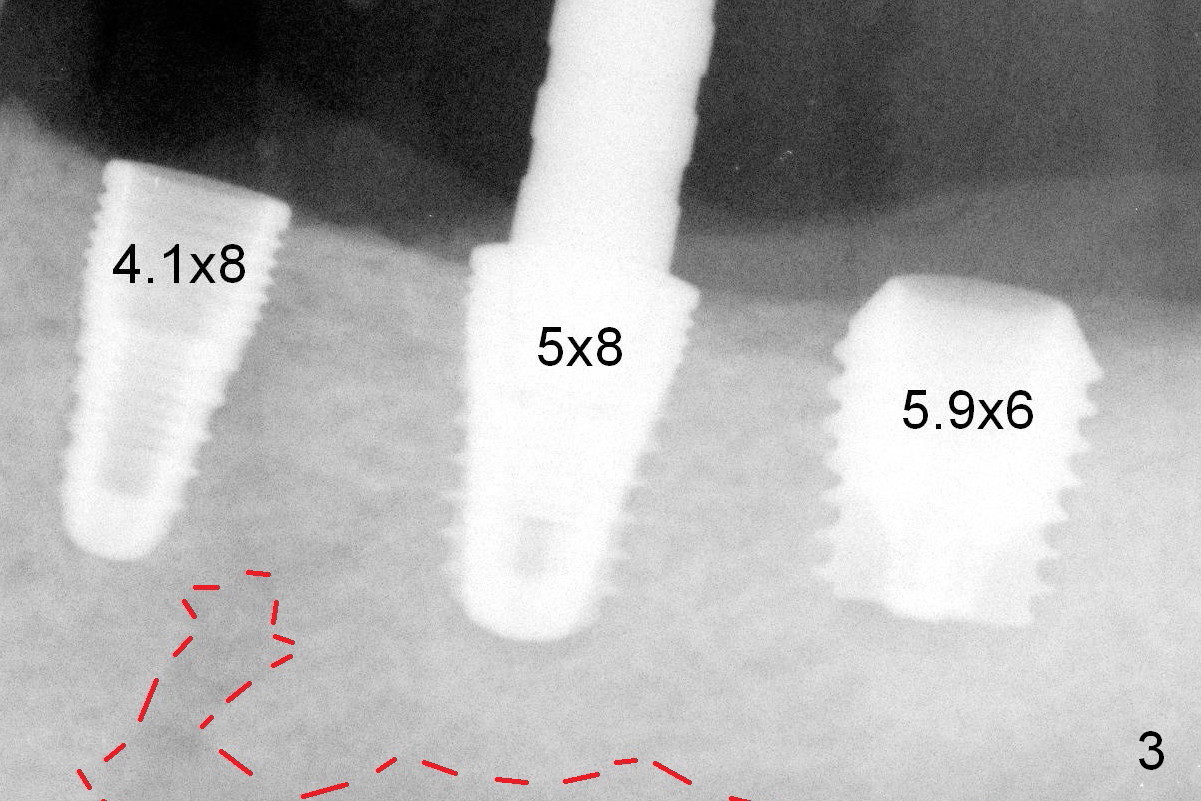

The size of the implants at the sites of #18-20 is shown in Fig.3 in millimeters. The insertion torque is around 50 Ncm. Red dashed line: the Inferior Alveolar Canal and Mental Foramen (loop). In fact the implants are not placed subcrestal, as compared to guided surgery at #29 and 30